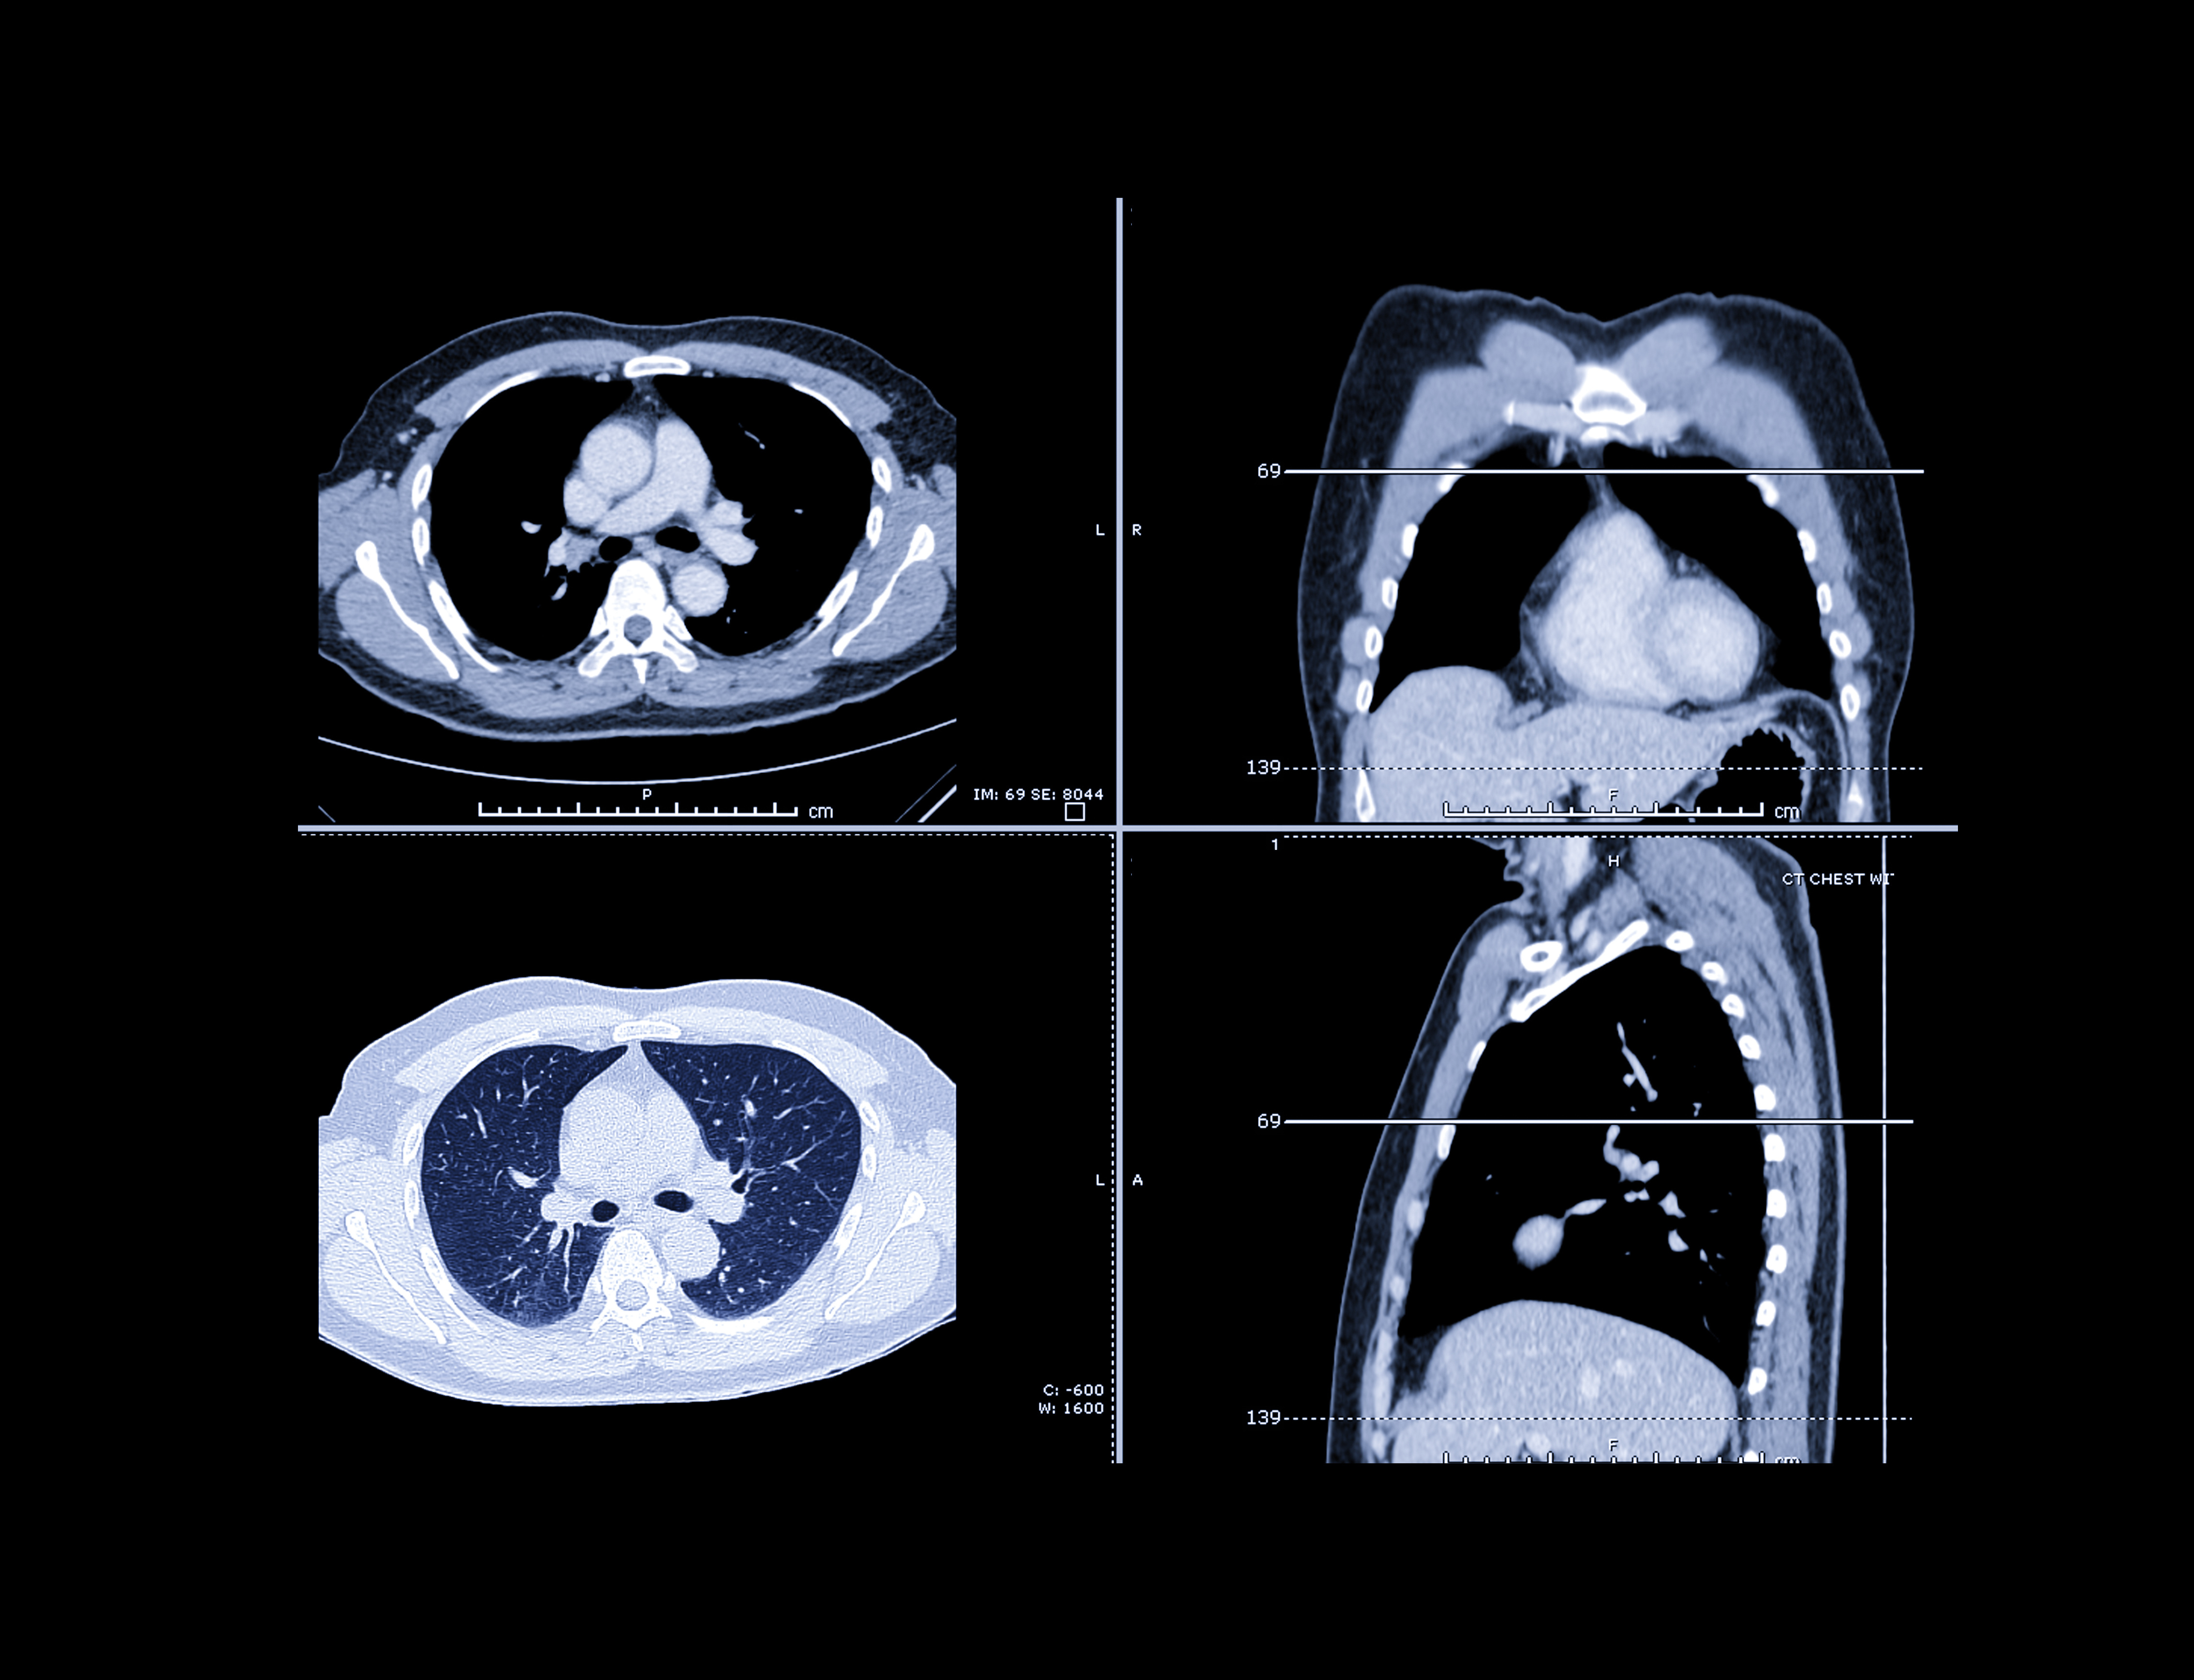

Serial CTRS is an AI-based prognostic tool that uses deep learning to analyze CT scans and stratify patients into high- or low-mortality risk categories. This aims to help clinicians optimize treatment decisions and perform surveillance of patients with metastatic non-small cell lung cancer.